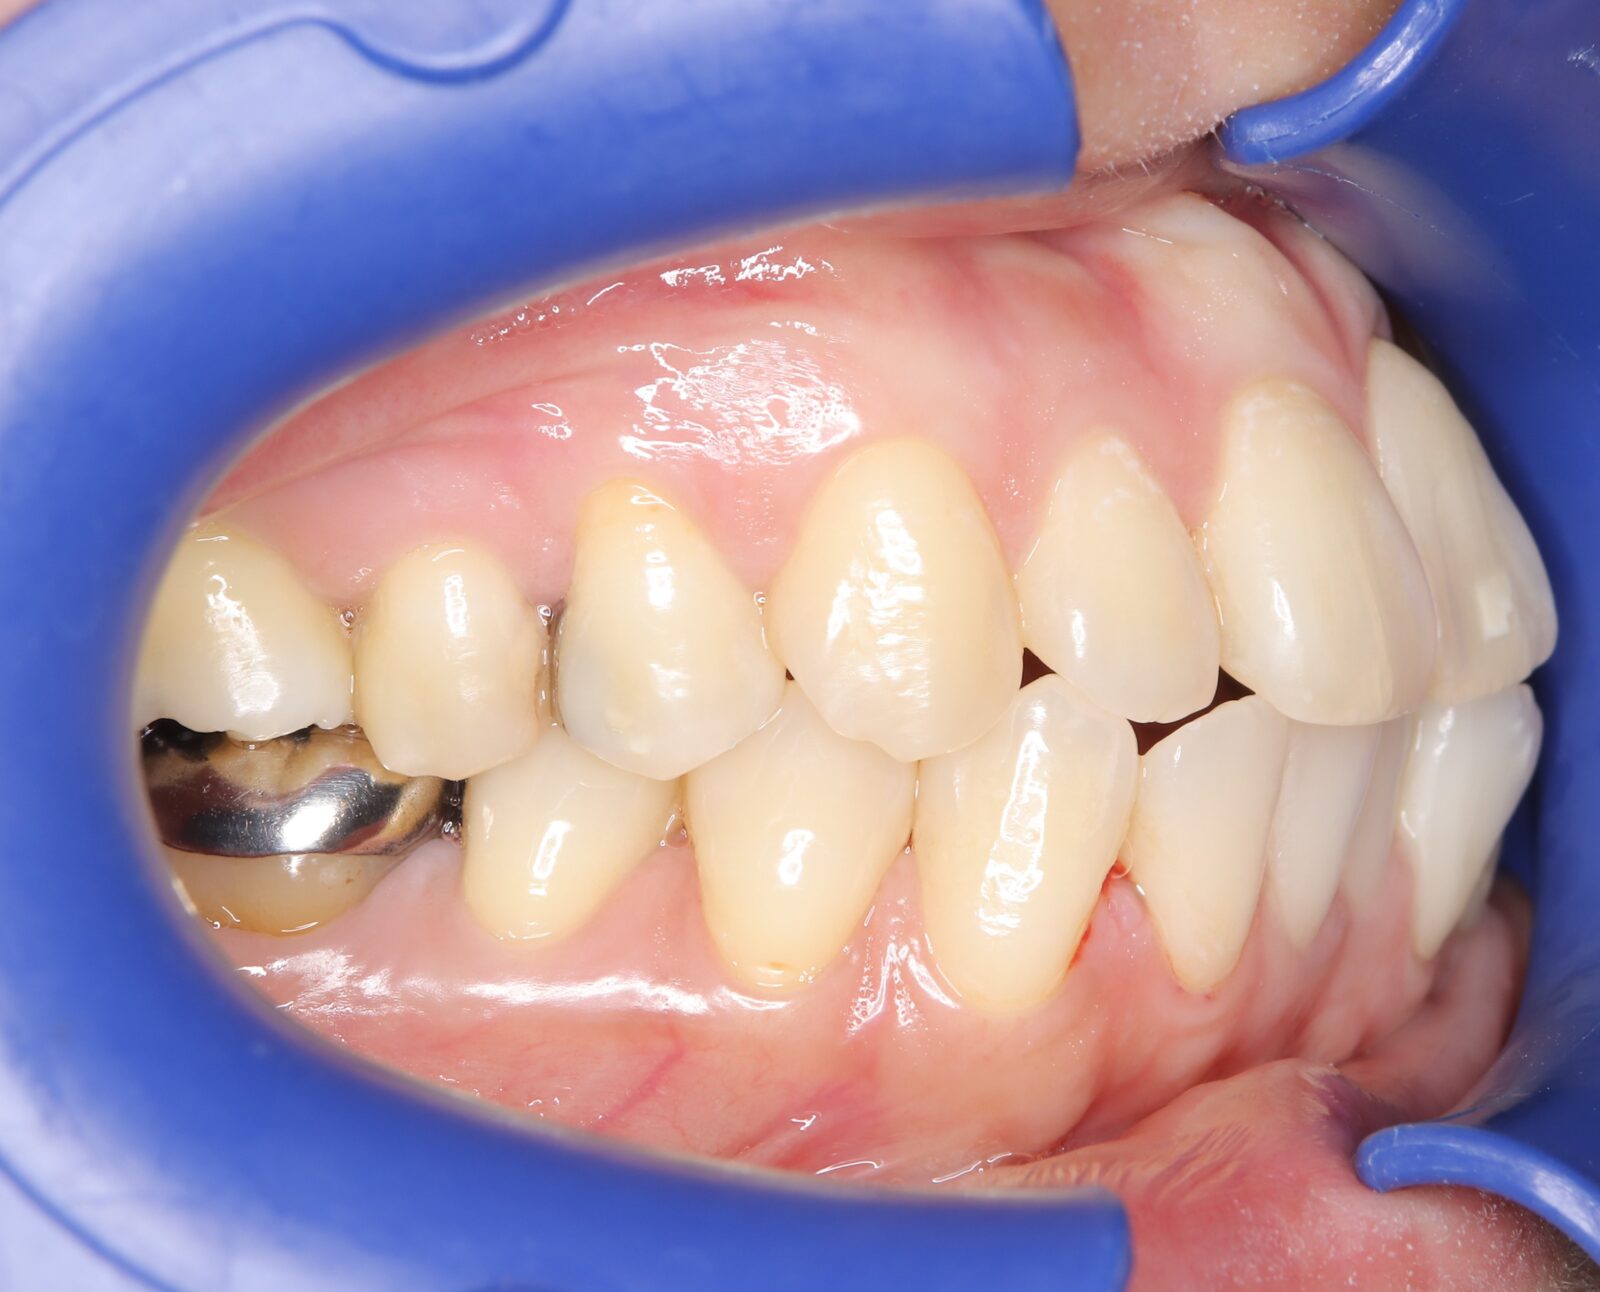

デンチャー+補綴+マウスピース矯正の症例

左上4〜7番に虫歯。右の親知らずの歯周ポケットは10mmあったため抜歯した。

左上6番の遠心は虫歯の範囲が大きすぎたため抜歯。義歯の安定を考慮すると、左上臼歯部をブリッジにするよりも、両側に義歯の人工歯を配置する方が良いと判断した。

本人の希望で薄く、口蓋を覆わない設計とした。

下顎前歯は抜歯後の治癒待ち、左上の虫歯治療中にインビザラインで歯列を整えた。

義歯作成期間中も歯の移動を行い、最終的には、計画通りに上顎の新義歯装着と同時に下顎のリテーナーを装着できた。

スマイルデンチャー

ジルコニアクラウン

インビザライン

治療期間約5ヶ月